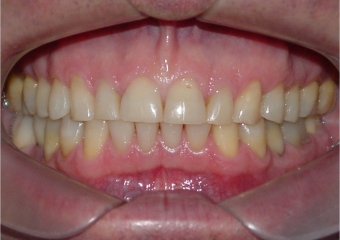

Mordida após a remoção do aparelho